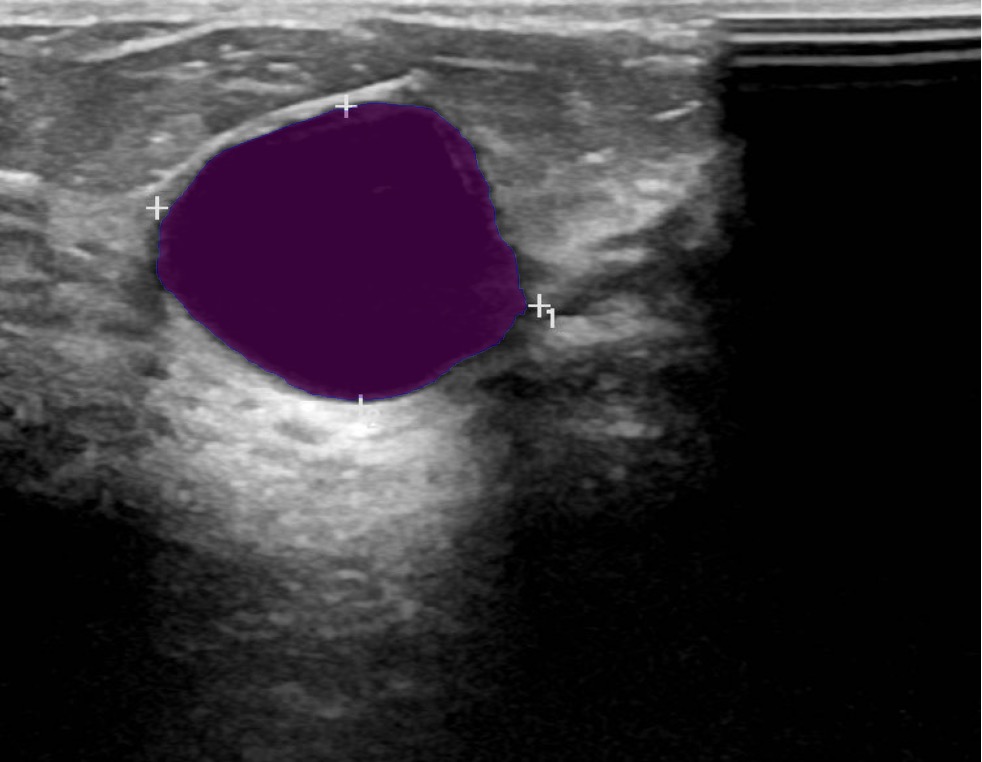

Figure 3: Sample outputs from various datasets showing regions of interest generated from SAM2.

Figure 3 shows the regions of interest generated by SAM2 for various datasets.